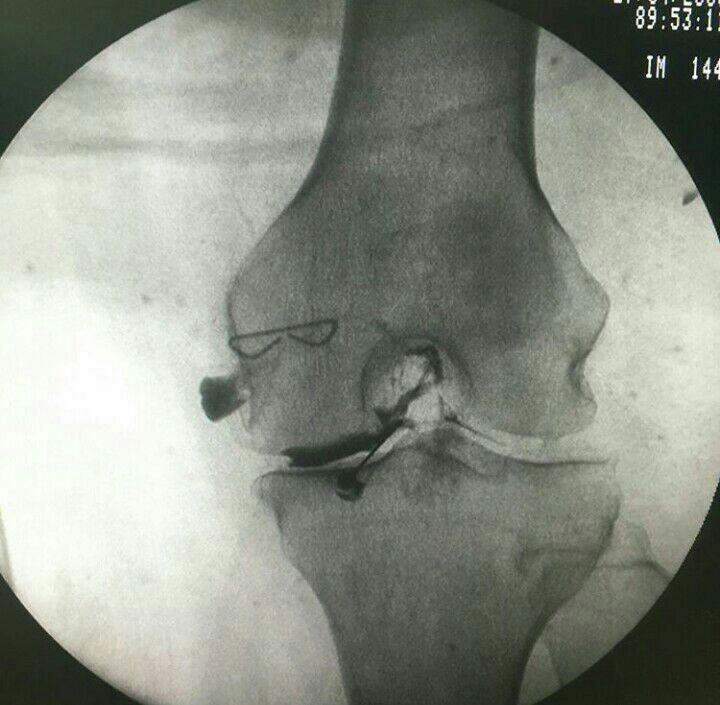

-درمان آرتروز مفاصل

-PRP و اوزون تراپی آرتروز مفصلی

دردهای اسکلتی عضلانی (کمردرد، گردندرد، زانودرد، آرتروز)